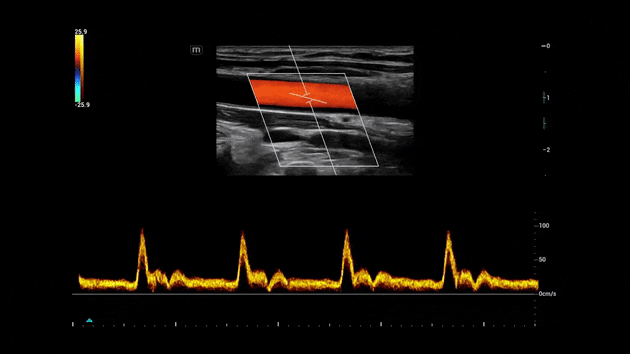

Strumento di tracciamento, misurazione e calcolo automatico

Riduce i tempi di misurazione tramite la tracciatura automatica dello spettro. Migliora la precisione e la riproducibilità del tracciamento dei margini spettrali.

Consona Series Cardiovascular Solution - Smart Calc feature clinical image

Regolazione automatica dell'angolo e della posizione della ROI

La funzionalità distintiva di Mindray che consente di ridurre i passaggi di scansione ripetitivi e dispendiosi in termini di tempo durante gli esami vascolari. Smart Track offre il rilevamento intelligente e in tempo reale dei vasi e l'ottimizzazione dell'immagine in tempo reale di Colore e PW.

Consona Series Cardiovascular Solution - Smart Track feature clinical image